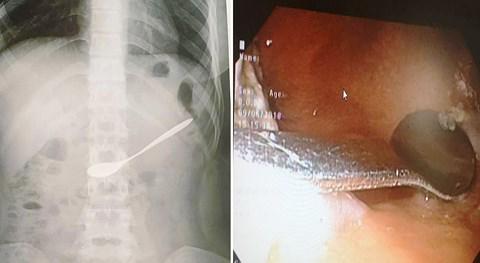

Ngày 10/6, thông tin từ Bệnh viện Đa khoa TP. Vinh (Nghệ An) cho biết, bệnh viện vừa tiếp nhận và gắp một chiếc thìa ra khỏi bụng một nữ bệnh nhân 20 tuổi.

Hình ảnh chiếc thìa nằm trong ổ bụng của bệnh nhân.

Trước đó, vào khoảng 12h trưa 9/6, chị L.T.N.A (20 tuổi, trú huyện Hưng Nguyên, Nghệ An) ngồi uống cà phê với bạn.

Trong lúc uống, chị A. không may bị bạn thúc vào tay nên đã vô tình đã nuốt chiếc thìa bằng kim loại vào họng. Do mắc vào họng, chị A. và bạn không lấy được ra nên thìa trôi vào bụng.

Ngay sau đó, chị A. được người bạn đi cùng đưa tới Bệnh viện Đa khoa TP. Vinh để cấp cứu.